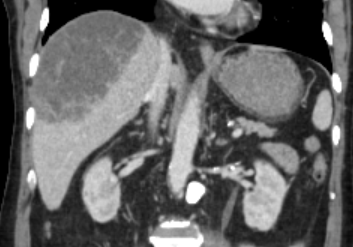

CT 촬영 결과는 충격적이었다.

환자의 우측 간의 절반정도가 농양화 되어 있었던 것이었다.

화농성 간농양의 양상을 보이고 있었고, 다행히 낮시간에 내원한 환자였기에 나는 곧바로 영상의학과 인터벤션 팀에 배농을 위한 경피적 삽관술을 의뢰하면서, 소화기내과로 환자 입원을 의뢰하였다.